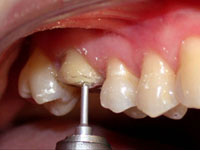

O ângulo cavo-superficial foi preparado com ponta diamantada (nº3118 da KG Sorensen) girando em baixa velocidade, formando um bisel chanfrado em toda extensão da margem vestibular e lingual do dente (Fig. 3). Por sua vez, as margens proximais foram biseladas com ponta diamantada de diâmetro menor (nº1111 da KG Sorensen) estendendo-se para vestibular e lingual com o intuito de manter o término cavitário separado do dente vizinho e manter a distância biológica horizontal (espaço para acomodar a papila sem ser comprimida, facilitar o acabamento das margens de esmalte, das bordas da restauração, a moldagem e o espaço para higienização) (Fig. 4 e 5).

Fig. 2

Vista por vestibular após a redução das cúspides.

Fig. 3

Determinação do bisel chanfrado ou côncavo vestibular com a ponta diamantada n°3118 (KG Sorensen).